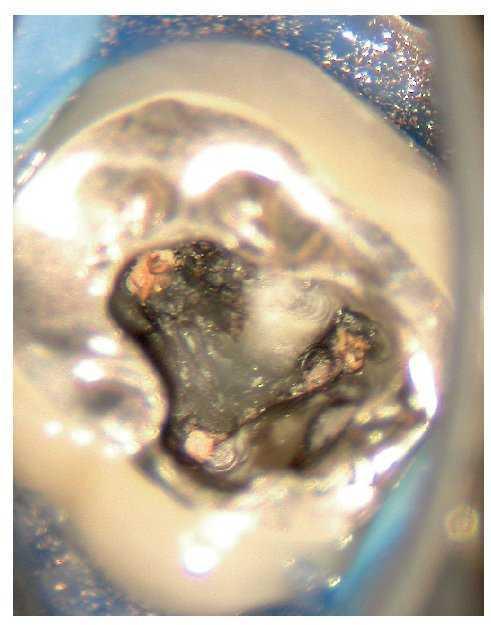

Figura 2c. Situación después de la apertura cameral: la obturación existente carece de sellado marginal. No se identificó la luz del conducto radicular original. Alrededor del material de obturación se detecta tejido necrótico de aspecto negruzco, sobre todo en la zona distal donde el conducto radicular adopta una forma marcadamente ovalada. Se pasó por alto y no se preparó el istmo frecuentemente existente en los molares inferiores entre el conducto mesiovestibular y el conducto mesiolingual.

Figura 2d. Después de limpiar el suelo de la cámara pulpar salen a la luz las estructuras del sistema de conductos radiculares que se pasaron por alto en el primer tratamiento.

Figura 2e. Situación después del retratamiento de los conductos principales. Se aprecia con claridad el tejido existente en el istmo mesial.

Figura 2f. Situación después de la preparación completa del istmo mesial coronal. Se pudo palpar otro istmo en el tercio medio de la raíz mesial a través del que fluyó líquido de irrigación. Se preparó este istmo mediante instrumentos ultrasónicos.